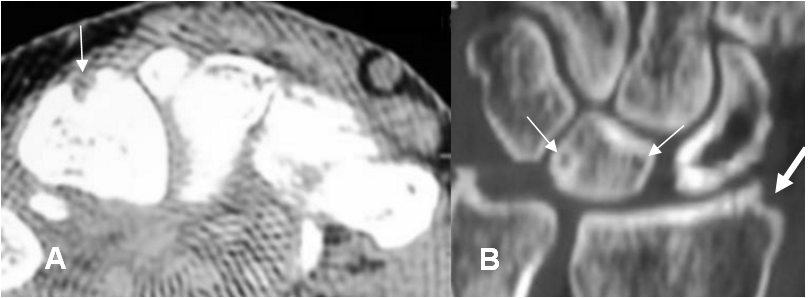

La detección de los cambios óseos es difícil, por la superposición de estructuras. Como la erosión es secundaria al compromiso del hueso cortical, su Dx es tardío. En estos casos el TAC puede ayudar, aunque no es una modalidad de primera línea. (6). (Fig 23).

Fig 23. Artropatía reumática en la mano.

A: TAC axial y B: TAC reconstrucción coronal. Erosiones en los huesos semilunar (Flecha delgada) y en el borde lateral del radio. (Flecha gruesa).